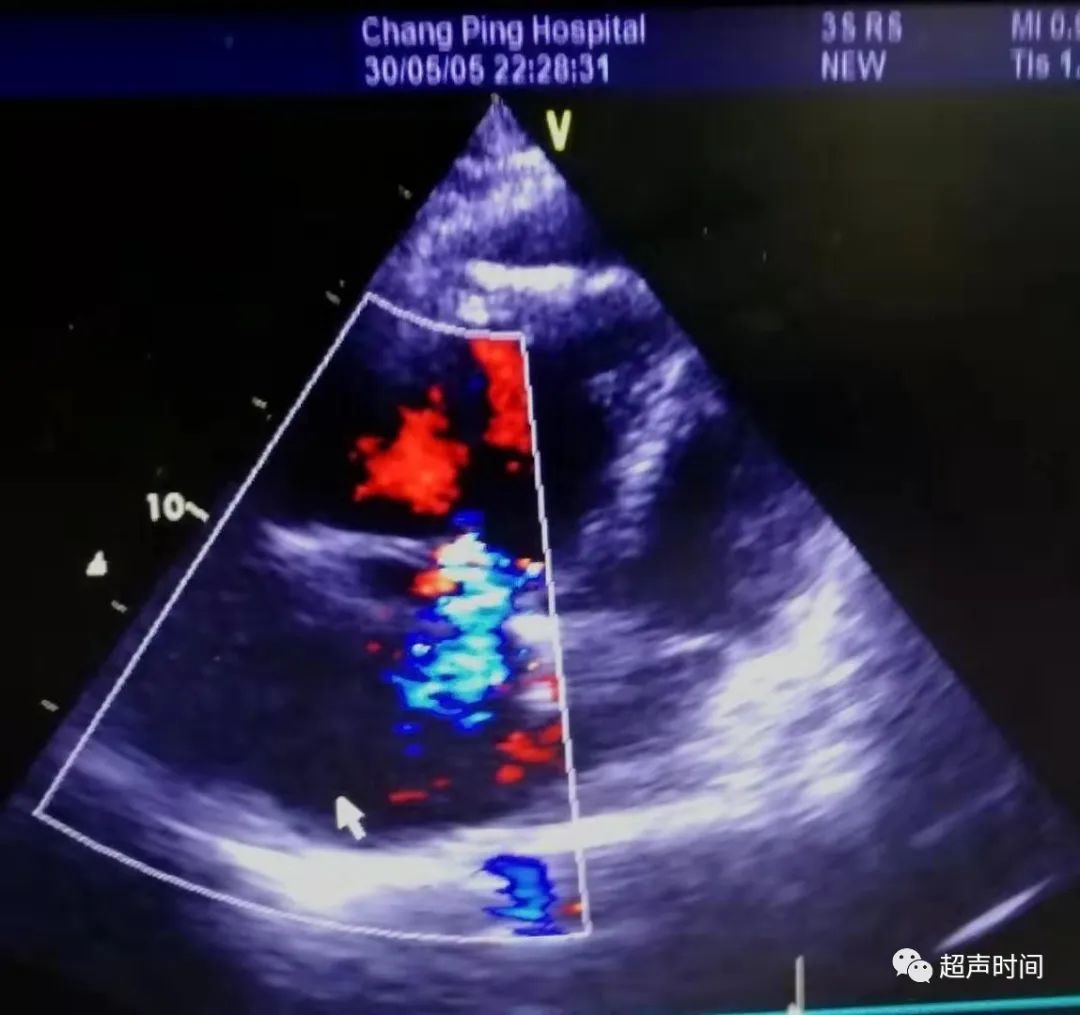

急诊床旁心脏超声所见如下:

图 3 和图 4 大动脉短轴切面显示右心房右心室增大,肺动脉扩张,左心室呈 D 型,充盈受限

图 5~图 7 四腔心切面显示右心明显增大,心尖区少量心包积液,三尖瓣大量反流,估测肺动脉收缩压 127 mmHg